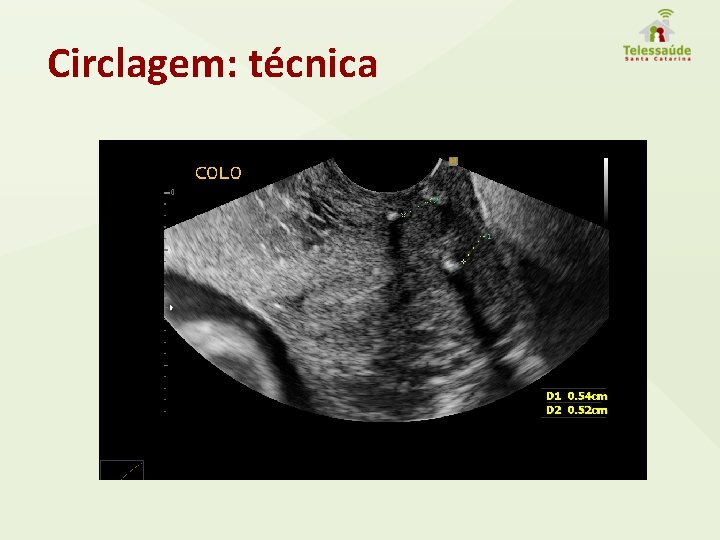

Circlagem: técnica

Avaliação ultrassonográfica do colo Técnica • Exame realizado entre 20 e 24 semanas; • Bexiga vazia; • Ideal: avaliação endovaginal com transdutor situado no fornix anterior; • Magnificação suficiente da imagem; • Identificar precisamente orifício interno e externo; • Mensuração linear, 3 tomadas dentro de 3 minutos, evitando pressão sobre o colo.

Circlagem Uma opção válida em casos selecionados. Oportunidade: idealmente até 16 semanas.